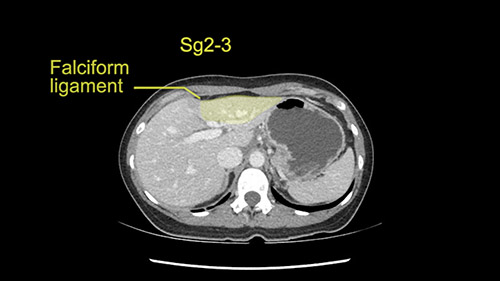

So if we look at the CT scan, on the axial, it’s a larger lesion. It’s about 6 or 7 or 8 centimeters. So it does look a bit threatening in terms of its resectability but if you really drill down deeply into the anatomy, and I think the coronal [imaging] is even better, you can see that the entire mass is on the patient’s left side of the falciform ligament. So it’s really only a left-sided tumor and not even really a left-sided tumor because Segment 4 is uninvolved anatomically.

None of the parenchyma is affected and this tumor is very exophytic; like many Hepatitis B hepatomas; and otherwise is resectable with either a wedge resection part of Segment 2-3 or a formal left lateral segmentectomy.

As I review the CT scan, we have both arterial and venous phases, the tumor is obvious. But I’ll start by saying that the liver itself does not appear to be cirrhotic to my eye. It’s got a normal contour and allied to that, that I do not see evidence of portal hypertension. The spleen is normal, there’s no collateral vessels. The tumor itself, I measured maximally at about 11 centimetres in diameter and I’m told the alpha fetoprotein is very high (over 10000), which is entirely consistent with this being a solitary hepatocellular carcinoma that is very exophytic. It seems to emanate off the inferior margin of Segment 3 (because that’s the falciform). I’ll start by saying that this is not transplantable. The tumor exceeds our guidelines for transplantation, but it's likely resectable based on normal liver and no portal hypertension.

So the issue with regards to resection. A left sided tumor. I believe I can see the falciform ligament right here so we’re looking at a resection of Segments 2, 3 of the left lobe of the liver. The left portal vein is right there. I think we’ll be wiser to take the left portal vein and therefore get well into Segment 4 and do a left hemihepatectomy. Certainly, one does not need to take the middle hepatic vein; it’s miles from the tumor.

Hi my name is Sedat Karademir. I’m from Ankara Guven Hospital and I’m an HPB and transplant surgeon. We are discussing about the case I reviewed the CT of 41 year old lady with a suspected hepatoma in the left lateral segment. Presumably its Segment 3. It looks like a big tumor sitting exophytically mostly out of the liver and pressing on the surrounding organs, but it doesn’t look like any invasion there. In this situation, according to the venous and arterial anatomy, it looks like this will be a Segment 2 and 3 resection.

The tumor is so close to the falciform ligament, I had a question mark about the Segment 4b relation between segment 4b and segment 3. In a normal resection of segment 2 and 3, we would be keeping on the left side of the falciform ligament and start getting segment 3 and 2 portal pedicles but in here its getting so close. So oncologically, 4b should be checked during the OR.